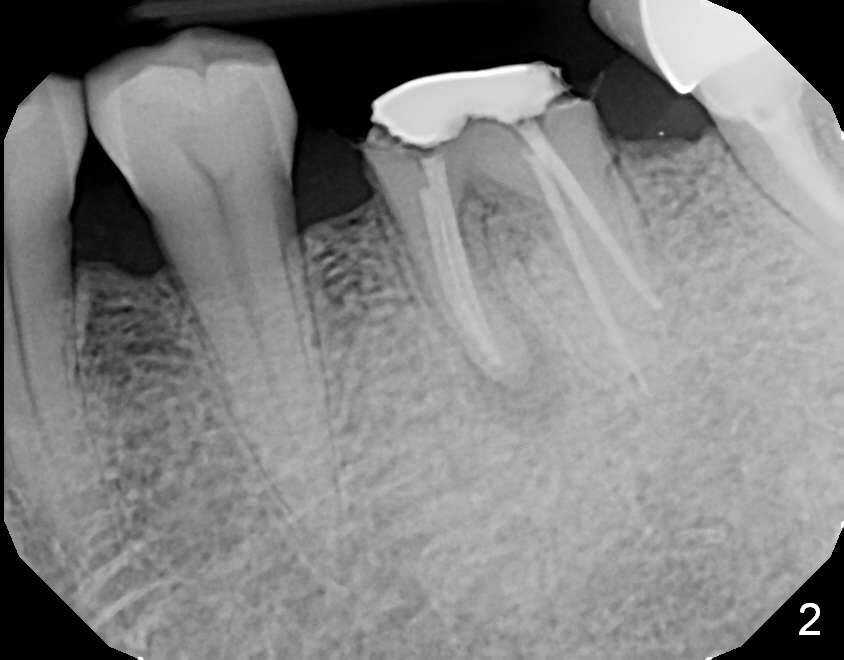

A 69-year-old man has pain in the tooth #19 (Fig.1). When a rubber dam clamp is placed for retreatment, the crown falls out (Fig2). Due to short clinical crown, the tooth is deemed non-salvageable. Fig.3 is an illustration after extraction. It seems that the septum is wide at the base. Measure socket depth. An osteotomy will be 1 mm longer than the socket depth (Fig.4). The osteotomy is initiated in the middle of the septum 14 mm deep. Insert a shortest parallel pin for occlusal check and a 14 mm long parallel pin for X-ray. Change trajectory if needed. A 5x14 mm tissue-level implant or 12 mm bone-level implant will be placed to prove that a short implant can achieve primary stability mainly by engagement into the septal struts and ~ 1 mm into apical new bone. With 2 roots distally, the position of the immediate implant will be affected?